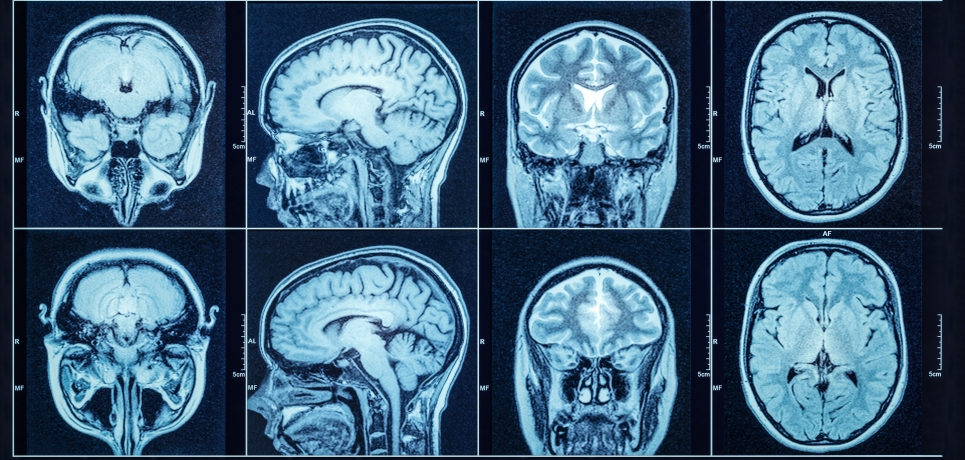

Imágenes por resonancia magnética

Razones para realizar la prueba Se puede realizar una resonancia magnética para diagnosticar un problema o buscar lesiones. Las resonancias magnéticas pueden observar cualquier parte del cuerpo. También se pueden usar para ver si un medicamento o tratamiento está funcionando para una enfermedad. Posibles complicaciones Los problemas son raros, pero todos los procedimientos tienen algúnContinue reading “Imágenes por resonancia magnética”